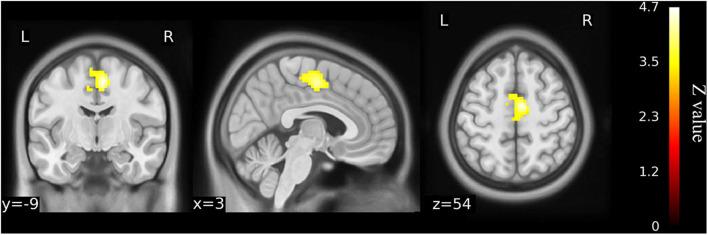

This study aimed to investigate the brain functional alterations with resting-state functional magnetic resonance imaging (rs-fMRI) in older patients with knee osteoarthritis (KOA) before and after total knee arthroplasty (TKA) and to assess the causal relationship of the brain function and neuropsychological changes. We performed rs-fMRI to investigate brain function of 23 patients aged ≥65 with KOA and 23 healthy matched controls. Of the KOA patients, 15 completed postoperative rs-fMRI examinations. Analyzes of the amplitude of low-frequency fluctuation (ALFF) and functional connectivity (FC) were used to estimate differences in brain functional parameters between KOA patients, postoperative patients, and the controls. The relationship between changes of pre- and post-surgical status in ALFF and neuropsychological test results was analyzed. Compared with the controls, all patients with KOA exhibited decreased ALFF in the default mode network (bilateral angular gyrus, precuneus gyrus, medial superior frontal gyrus) and increased ALFF in the bilateral amygdala and cerebellum posterior lobe before surgery ( < 0.001). Altered ALFF persisted in the same brain regions 1 week postoperatively. The decreased ALFF in the left precuneus gyrus and middle temporal gyrus was found after surgery when compared with preoperative data ( < 0.01). Preoperatively, the KOA patients exhibited increased FC between the left precuneus gyrus and the right supplementary motor area compared to the controls ( < 0.001), but this connectivity became no significant difference after TKA. The left Cerebelum_9 was found to have decreased FC with the right precuneus gyrus postoperatively ( < 0.001) although this was not significantly different before surgery. The significantly altered ALFF values were not correlated with changes in cognitive assessment scores. In older patients with end-stage KOA, functional alterations in important brain regions were detected with the persistence and further changes observed at an early stage after knee replacement. Our data further our understanding of brain functional abnormalities and cognitive impairment in older patients following knee replacement, which may provide therapeutic targets for preventive/treatment strategy to be developed. Clinical Trial Registration: http://www.chictr.org.cn/index.aspx, ChiCTR1800016437; Registered June 1, 2018.

本研究旨在通过静息态功能磁共振成像(rs-fMRI)调查老年膝骨关节炎(KOA)患者全膝关节置换术(TKA)前后的脑功能改变,并评估脑功能与神经心理变化之间的因果关系。我们对23例年龄≥65岁的KOA患者及23名匹配的健康对照者进行rs-fMRI以研究脑功能。其中15例KOA患者完成了术后rs-fMRI检查。采用低频振幅(ALFF)分析和功能连接(FC)分析来评估KOA患者、术后患者及对照者之间脑功能参数的差异。分析了手术前后ALFF变化与神经心理测试结果之间的关系。与对照组相比,所有KOA患者术前默认模式网络(双侧角回、楔前回、额上回中部)的ALFF均降低,双侧杏仁核和小脑后叶的ALFF增加(<0.001)。术后1周,相同脑区的ALFF改变持续存在。与术前数据相比,术后发现左侧楔前回和颞中回的ALFF降低(<0.01)。术前,与对照组相比,KOA患者左侧楔前回与右侧辅助运动区之间的FC增加(<0.001),但TKA术后这种连接性无显著差异。术后发现左侧小脑_9与右侧楔前回的FC降低(<0.001),尽管术前无显著差异。ALFF值的显著改变与认知评估评分的变化无关。在老年终末期KOA患者中,检测到重要脑区的功能改变,且在膝关节置换术后早期观察到这些改变持续存在并进一步变化。我们的数据进一步加深了我们对老年患者膝关节置换后脑功能异常和认知障碍的理解可能为制定预防/治疗策略提供治疗靶点。临床试验注册:http://www.chictr.org.cn/index.aspx,ChiCTR1800016437;2018年6月1日注册。